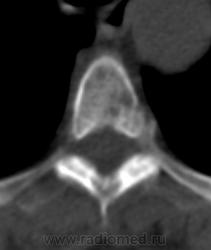

Костное окно:

Я всегда с интересом отношусь к "высоким технологиям", но, как свидетельствуют данные, картинка тел пораженных позвонков при миеломе очень напоминает "картинку мозга"...

По имеющимся файлам-дайком я не нашла признаков опухоли. Имеется множественное остеолитическое поражение позвоночника, ребер, грудины, частично - таза. Лимфоузлы не увеличены. Тоже поставила бы на первое место миеломную болезнь. Диагностирование её не всегда простое дело. Поражена грудина и, наверное, нужно посоветоваться с онкологом (гематологом) стоит ли сделать стернальную пункцию.Советую написать в личку tatyana.